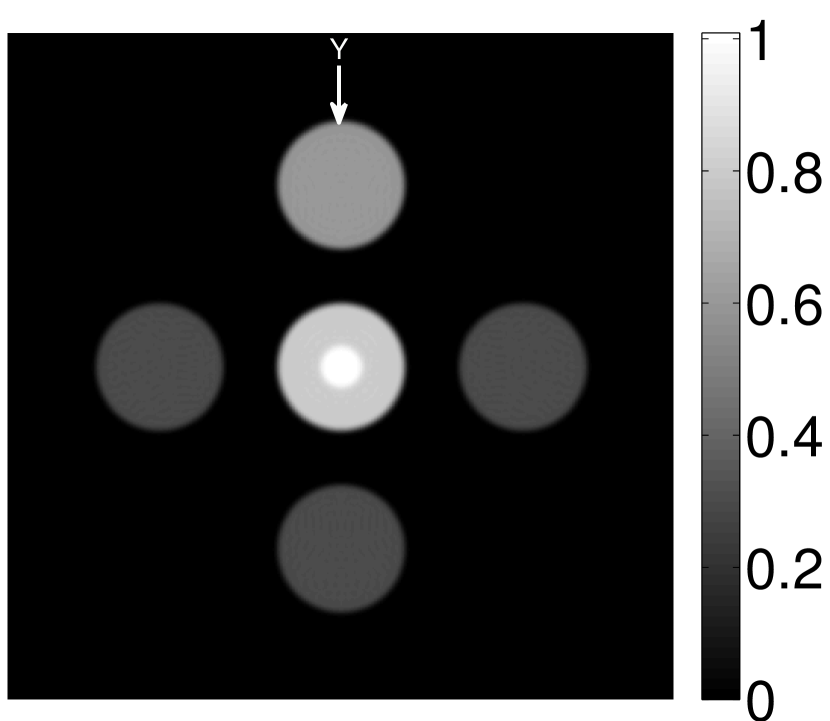

The numerical phantom shown in Figure 1(a) was employed. The phantom had a support area of mm2 and contained six uniform disks that were assigned different values of absorbed optical energy density.

A 2D circular measurement geometry was employed. transducers were evenly distributed on a ring of radius mm that enclosed the phantom. The SOS was assumed to be constant and set at mm/s. Since the simulated data were formed by use of the C-D imaging model in Eqn. (2), no inverse crime was committed. The components of this vector corresponded to equally spaced temporal samples over the interval s. Subsequently, the noiseless voltage vector was obtained by convolving the pressure data with EIR-1 in Figure 1(b).

The reconstruction region ( mm2) was represented by pixels with pixel size mm in each dimension. The initial guess of the EIR employed in the VP algorithm was different than the EIR that was assumed when generating the simulated data. This served to simulate a situation in which an experimentally measured EIR contained errors.

Each element in a real-world transducer array possesses its own EIR. In practice, the differences between the EIRs are sometimes neglected and an EIR corresponding to a single element may be used to represent all elements in the array. In some of the studies below, the EIR employed to initialize the VP algorithm (EIR-2 in Figure 1(b)) and the EIR employed to produce the simulated measurements (EIR-1 in Figure 1(b)) were experimentally measured from two different transducer elements in a circular transducer array (see Sec. VI-B). EIR-1 was measured by temporally integrating the PA signal produced by a point source positioned at the focus of the transducer. EIR-2 was measured by use of the method reported in [RNR2011]. In order to investigate the sensitivity of the VP algorithm to the initialization of the EIR, we employed different EIRs obtained by degrading EIR-1 as described later. When solving the sub-problem in Line-2 of Algorithm 1, was initialized as the zero vector. Algorithm 1 was terminated after 500 iterations, since it was observed that the changes in the reconstructed images with more iterations were negligible. When implemented by use of a single core of an Intel Xeon E5-2640 CPU, each iteration required approximately 7s to complete.

Figure 2(a) shows the image reconstructed by use of the conventional iterative method that utilized a system matrix based on EIR-2. Different values of the regularization parameter from the interval were considered. The reconstructed image with the value of that minimized the RMSE was chosen to represent the best performance of the conventional iterative method. Figure 2(a) and the profile in Figure 2(c) demonstrate that the use of an inaccurate EIR can result in strong artifacts and distortions in images reconstructed by use of the conventional methods.

When the VP algorithm was applied, different values of the regularization parameter from the interval and from the interval were considered. The image that minimized the RMSE was chosen and displayed in Figure 2(b). As revealed by this image and the profiles in 2(c), the VP algorithm yielded an image with fewer artifacts and distortions, and image fidelity was improved as reflected by the reduced RMSE.